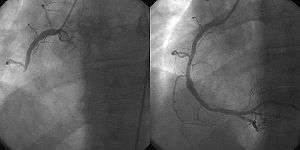

A large number of procedures can be performed on the heart by catheterization. This most commonly involves the insertion of a sheath into the femoral artery (but, in practice, any large peripheral artery or vein) and cannulating the heart under X-ray visualization (most commonly fluoroscopy). The radial artery may also be used for cannulation; this approach offers several advantages, including the accessibility of the artery in most patients, the easy control of bleeding even in anticoagulated patients, the enhancement of comfort because patients are capable of sitting up and walking immediately following the procedure, and the near absence of clinically significant sequelae in patients with a normal Allen test.[2]

The main advantages of using the interventional cardiology or radiology approach are the avoidance of the scars and pain, and long post-operative recovery. Additionally, interventional cardiology procedure of primary angioplasty is now the gold standard of care for an acute myocardial infarction. It involves the extraction of clots from occluded coronary arteries and deployment of stents and balloons through a small hole made in a major artery, which has given it the name "pin-hole surgery" (as opposed to "key-hole surgery").

- Also called percutaneous coronary intervention (PCI), angioplasty is an intervention for the treatment of coronary artery disease.